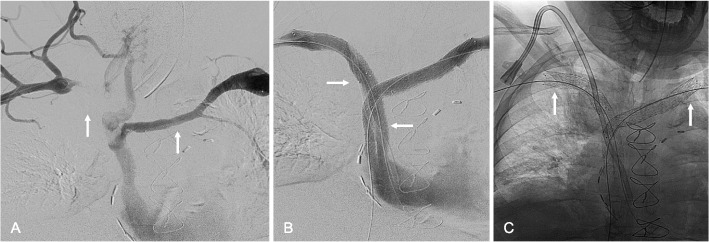

Methods: Thirty-eight patients (43 affected limbs) with symptomatic ASVT and no prior treatment or surgical decompression underwent endovascular placement of dedicated venous stents across the thoracic outlet with Abre Venous Stents (Medtronic, Dublin, Ireland), Venovo Venous Stents (BD, Franklin Lakes, NJ, USA), or Vici Venous Stents (Boston Scientific, Marlborough, MA, USA). Stents were extended peripherally to the subclavian or axillary veins and centrally to the brachiocephalic vein or SVC. Technical success was defined as successful stent deployment across the costoclavicular space, and clinical success as symptomatic improvement.

Results: Stent placement was technically successful in all 43 limbs (100%), with clinical improvement observed in 97.4% of patients. The one patient without clinical improvement experienced early thrombosis of the stent, requiring mechanical thrombectomy and additional stenting. Follow-up CT venography at a mean of 301.3 days demonstrated high primary stent patency rates (81.4%), with stent crushing observed in only 7.0% of limbs and no instances of stent fracture. Adverse events were limited, including two access site hematomas and one hypotensive episode, all of which resolved without evidence of long-term complications.